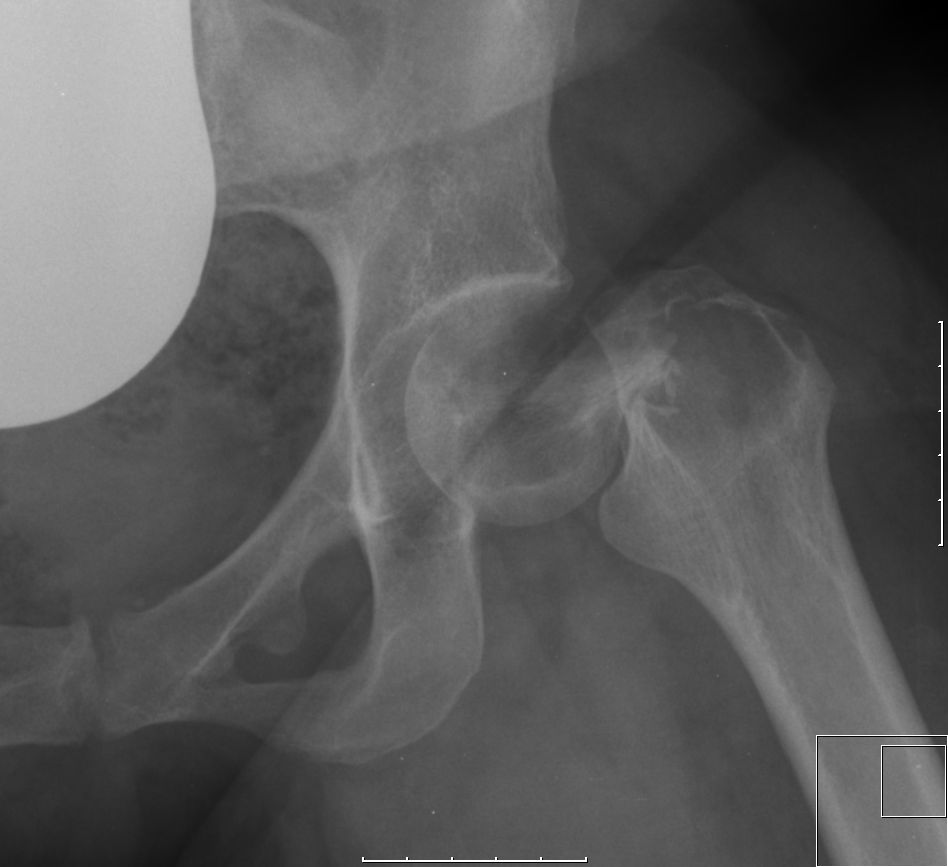

Klinik Wächst lokal destruierend. Im Röntgen zeigt sich typischerweise eine exzentrische lytische Knochenläsion. MRT ist wichtig, um vor einer Operation die Ausdehnung im Knochen und in dem umgebenden Weichteilgewebe festzustellen.

Fälle 28-jährige Frau mit Spontanfraktur des linken Schenkelhalses.